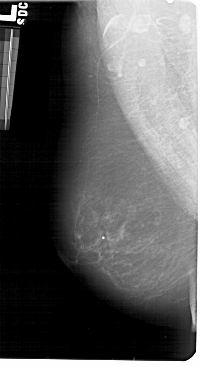

A_1428_1.RIGHT_CC

LEFT_CC LINES 5431 PIXELS_PER_LINE 2581 BITS_PER_PIXEL 12 RESOLUTION 43.5 NON_OVERLAY